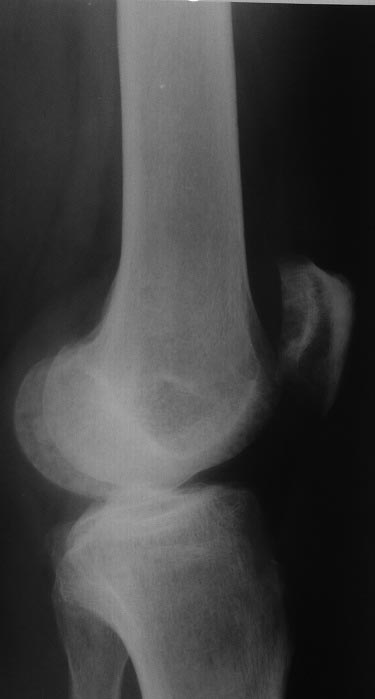

[Ortho] Остеомиелит надколенника

фото

Имя     : 12.jpg

Тип     : image/jpeg

Размер  : 31408 байтов

Url     : http://weborto.net:8080/pipermail/ortho/attachments/20171230/997926fb/attachment-0004.jpg